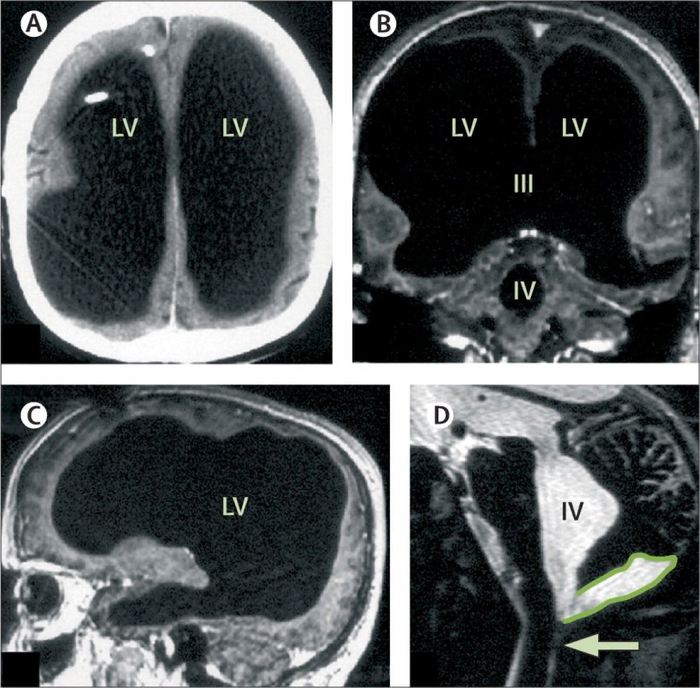

Человек живет без мозга!

Во Франции случайно обнаружили работягу, у которого нет 90% мозга. Случилось это еще в 2016 году: 44-летний мужик обратился в больницу с болью в ноге, но на МРТ обнаружили, что череп заполнен жидкостью, а от мозга остался лишь тонкий слой коры Оказалось, что работяга жил обычной жизнью и даже не подозревал о недуге: у него есть семья и работа, показатель IQ 84 (ниже среднего), но он социально приспособлен и дружелюбен, несмотря на отсутствие большей части мозга